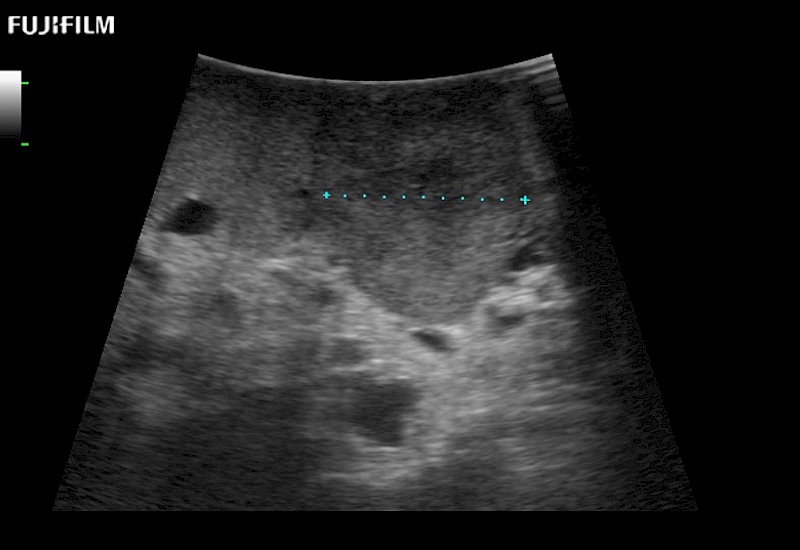

Exclusive linear array robotic surgery transducer.

Features:

Main Specifications: